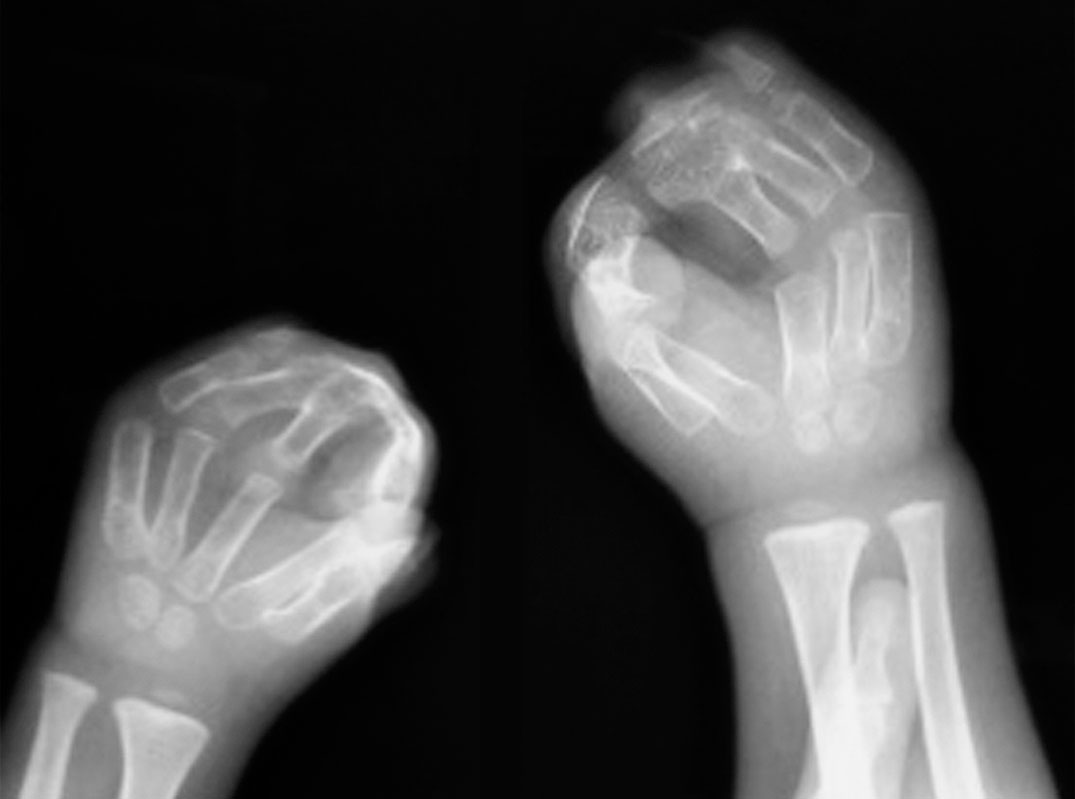

A.右手镜影手(患手共7 个手指);B.X 线片显示双尺骨畸形

镜影手患儿多同时表现为双尺骨畸形(图1-2-40)。